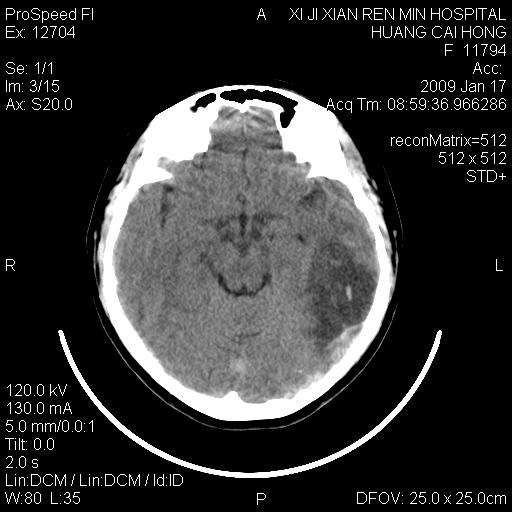

以下是引用zbp537在2009-1-19 13:54:00的发言:[br]首先考虑脑炎。[br]诊断依据:[br]1、患者较年轻。[br]2、有感冒病史。[br]3、左侧颞枕叶这么大一片低密度影,占位征象却不明显,不符合肿瘤特征,其内的高密度影为出血灶。

以下是引用xiaoniu在2009-1-19 13:29:00的发言:[br]左侧颞叶三角形低密度影,占位效应不明显,其内点片样高密都影,青少年患者,首先考虑:少突胶质瘤。因为有感冒病史,不能除外感染的可能。